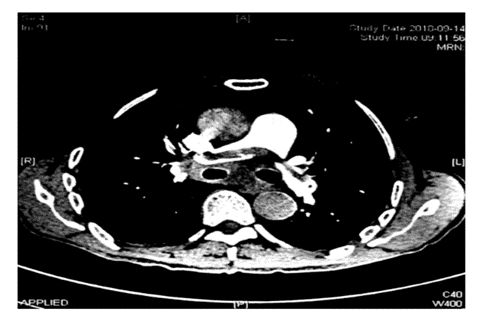

肺动脉CT(图3)证实为肺动脉骑跨栓。

心电图怎么切换导联原来读懂心电图可以如此简单!_https://www.jmylbn.com_新闻资讯_第7张

图3:患者行肺动脉CT检查

T波倒置的产生可以有很多原因,如心肌缺血、右心系统疾病、微循环障碍等等,对比患者之前的心电图,发现T波存在着动态变化,结合患者长期卧床的病史,急查D-Dimer示升高,经肺动脉CT证实为肺动脉骑跨栓。